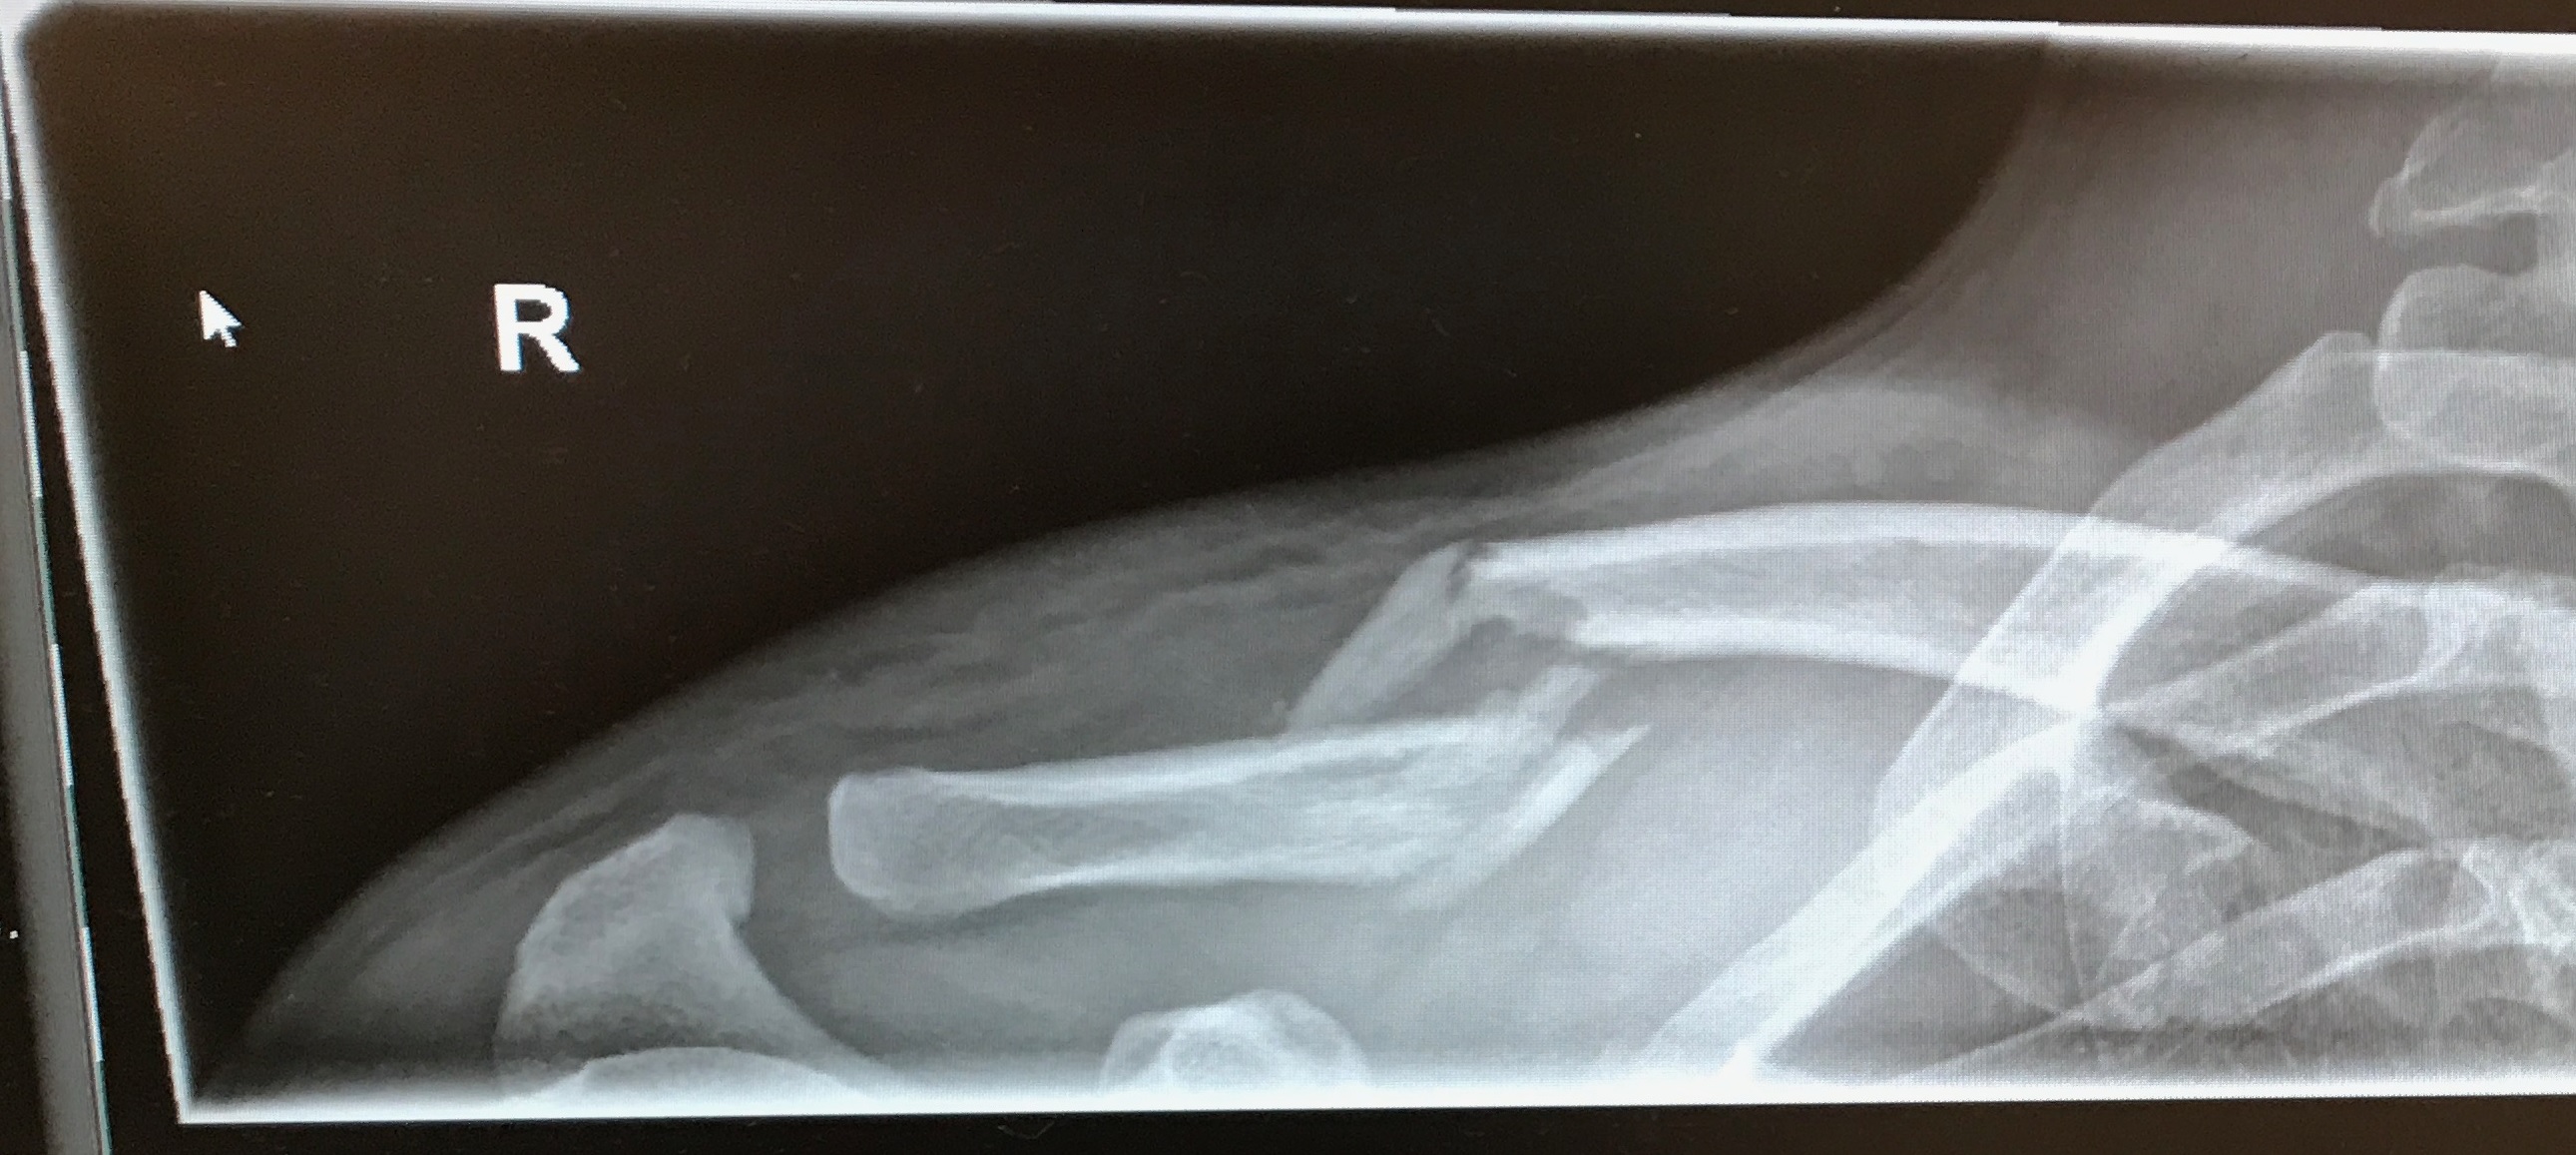

SB2.jpg

SB1.jpg

Hast du deine Platte schon rausbekommen? Von den Bildern her könnte es mein Bruch sein, sogar die gleiche Seite :roll:

Mittig an dem Splitterbruch ist das Schlüsselbein inzwischen auch gut doppelt so dick wie an der gesunden anderen Seite, daher kann ich die Aussage das der Knochen nach einem Bruch stabiler ist gut nachvollziehen :lol: